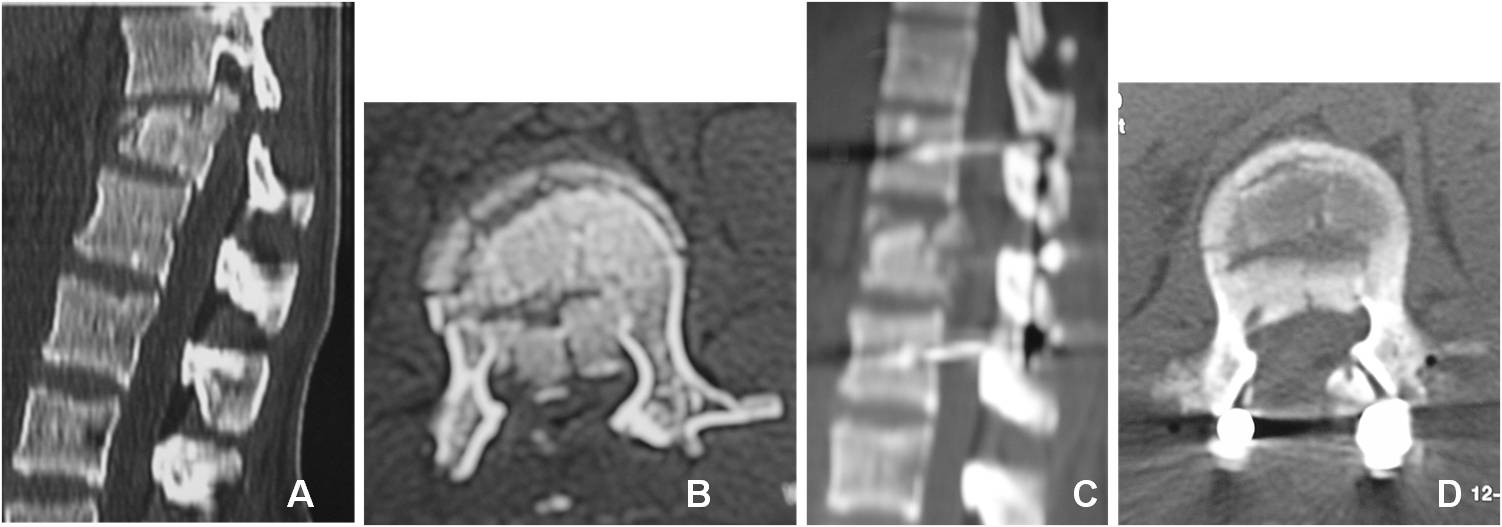

Introducción: El tratamiento quirúrgico de las fracturas toracolumbares es controvertido. La vía de abordaje y la cantidad de niveles de instrumentación son motivo de debate. El objetivo de este estudio fue analizar los resultados radiológicos y clínicos de pacientes con fracturas toracolumbares por estallido y flexión/distracción.MaterialesyMétodos: Estudio retrospectivo de una serie consecutiva de pacientes tratados quirúrgicamente entre 2004 y 2008, con seguimiento >12 meses. Se incluyeron pacientes con instrumentación y artrodesis corta de los niveles adyacentes a la lesión, abordados por vía posterior. Se tomaron en cuenta fracturas de tipo A3 y B de la clasificación AO. Se llevaron a cabo evaluaciones clínica, neurológica y radiológica.Resultados: Se registraron 25 pacientes, 3 se perdieron en el seguimiento y 22 fueron analizados. El promedio de edad fue de 37 años. La causa más frecuente fue caída de altura, seguida de accidente vehicular. El nivel más afectado fue L1. El promedio de cifosis preoperatoria fue de 14º y de 4º en el posoperatorio alejado. En la evaluación clínica, 10 pacientes tuvieron un excelente resultado; 10, bueno y 2, regular. No hubo compromiso neurológico en 21 pacientes.Conclusiones:La instrumentación corta proporciona muy buenos resultados en la mayoría de los pacientes tanto a nivel radiológico como funcional. La selección de los pacientes debe ser estricta, se debe excluir a aquellos con cifosis grave, conminución importante u otro factor que haga pensar en la necesidad de un abordaje anterior. En el seguimiento alejado, no se observa una pérdida significativa de la reducción en la cifosis.Descargas